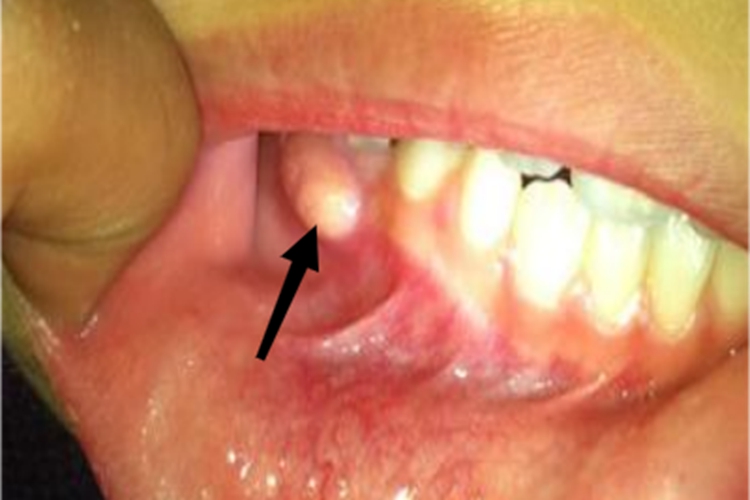

炎症初期可感觉牙龈处有发胀、发痒等表现,局部肿胀。局部化脓后,可有自发性的钝痛,咀嚼时疼痛加重,可在牙龈部位形成隆起的脓疱。

仅有轻度的不适感,一般无明显的疼痛,牙龈部位可出现根尖周囊肿。